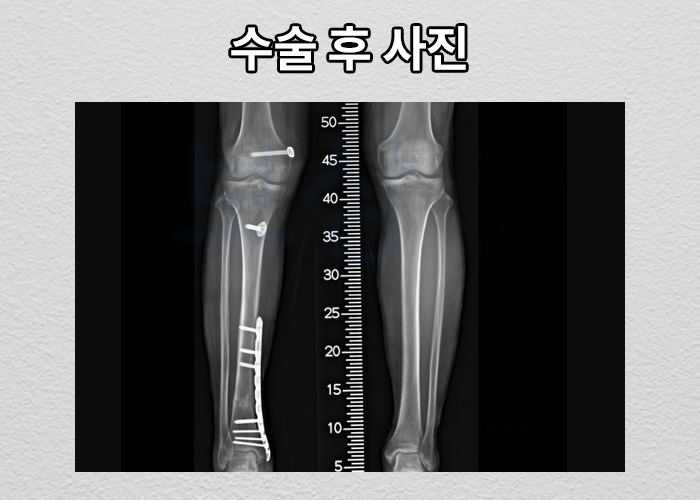

후방 십자인대 파열로 재건술까지 받아 요양이 필요하셨던 의뢰인입니다. 사실 의뢰인은 무릎 인대 파열 뿐 아니라 경비골 골절로 인해 발목의 각도도 잘 나올지 검토해보아야 하는 상황이었죠.